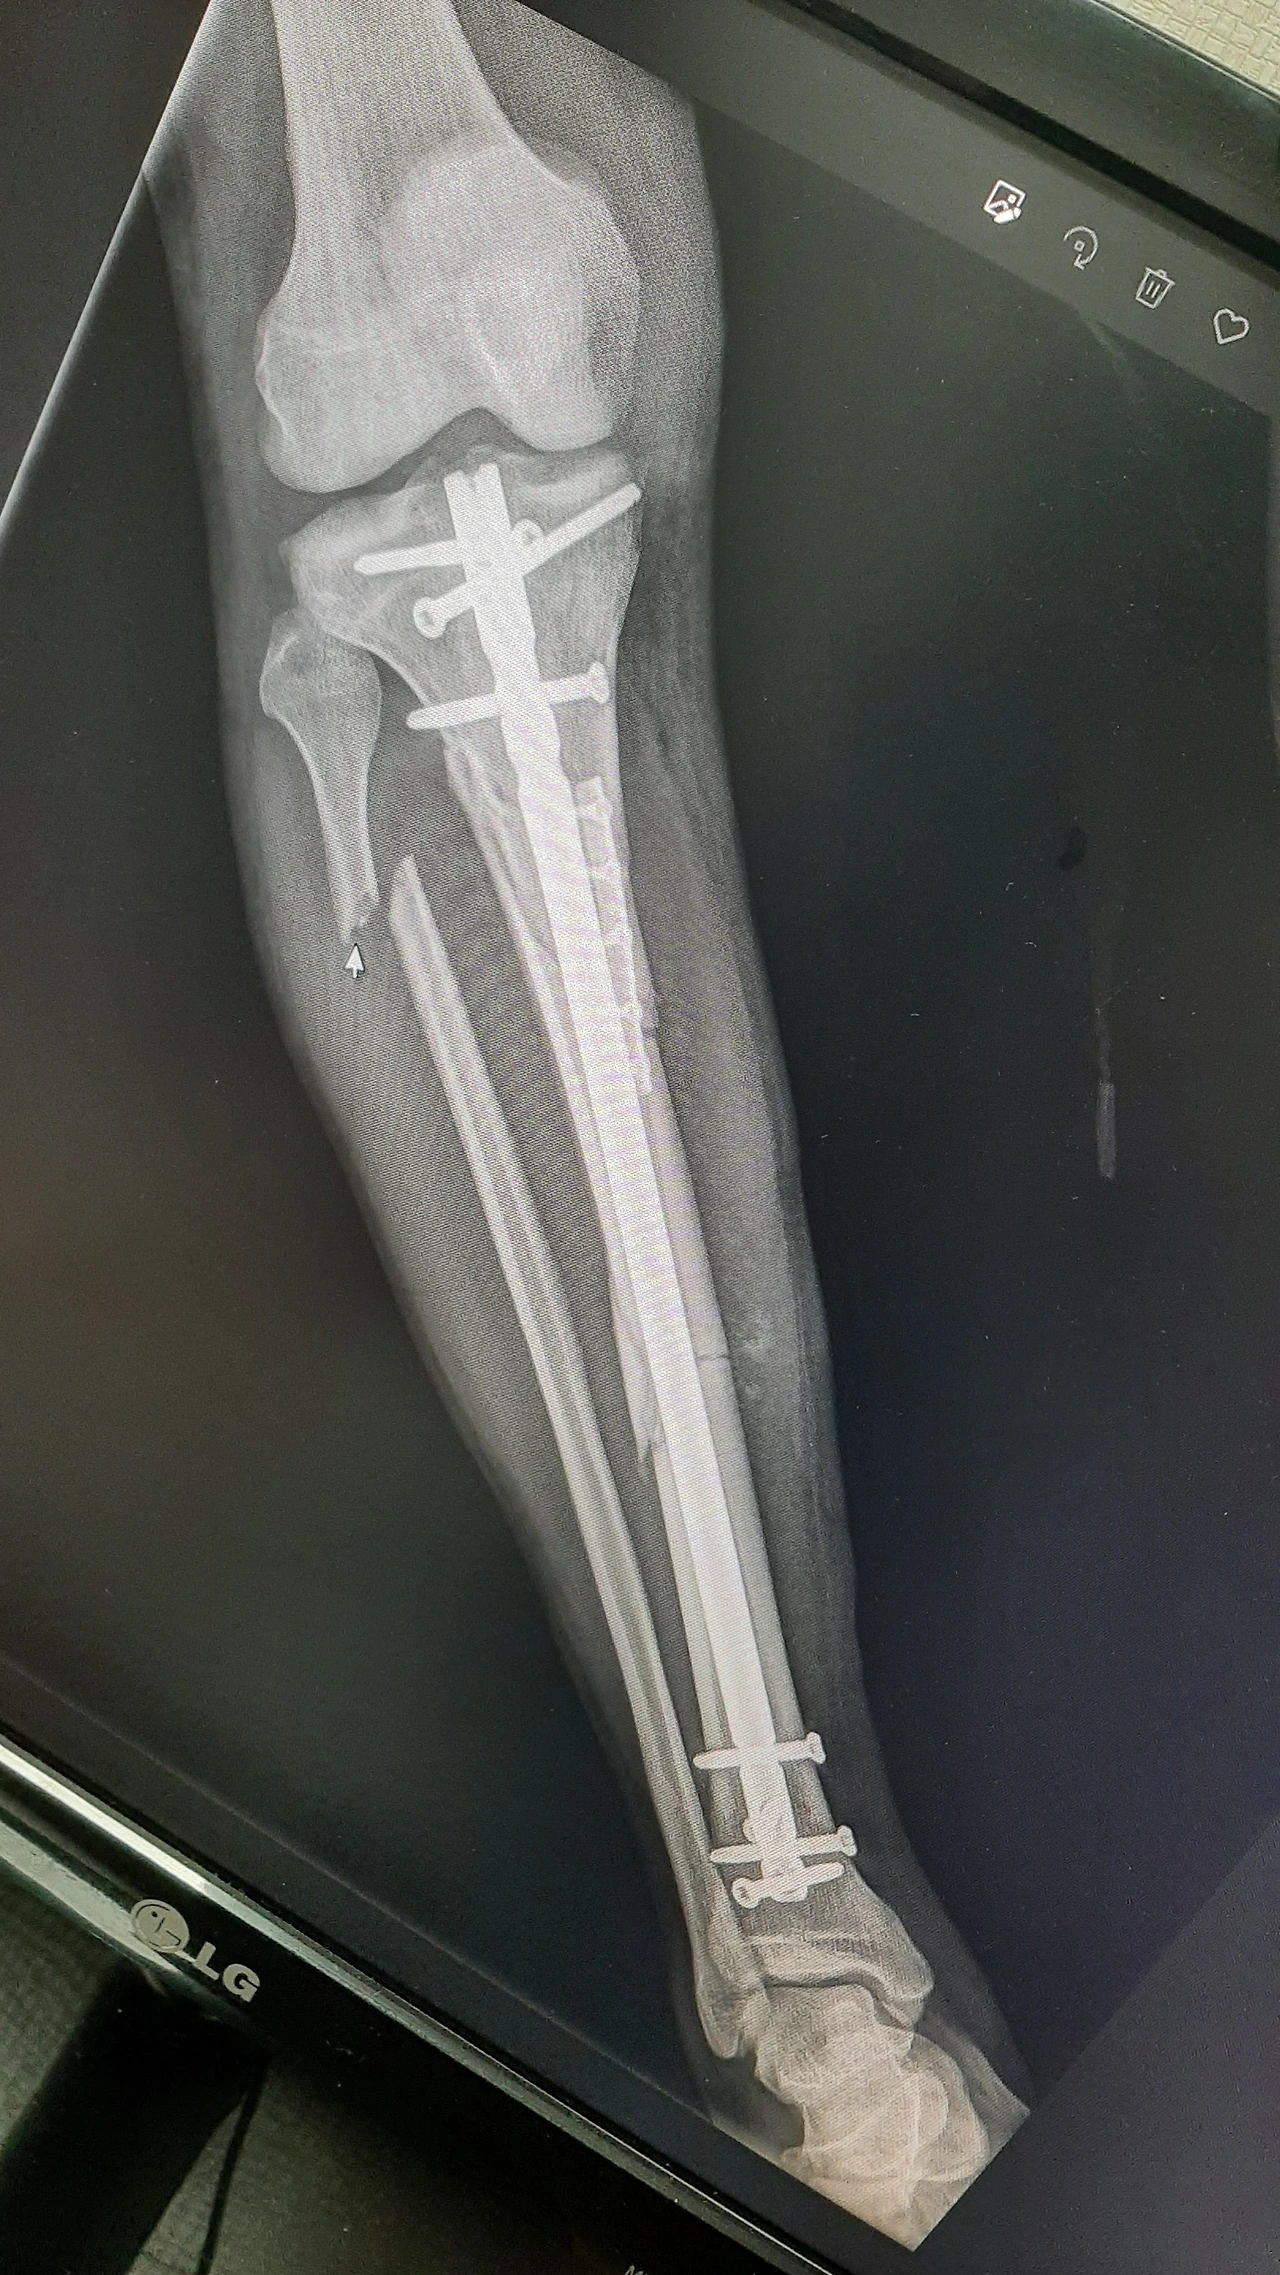

2022년 7월 13일 골절 당시

2022년 7월 20일 수술 후